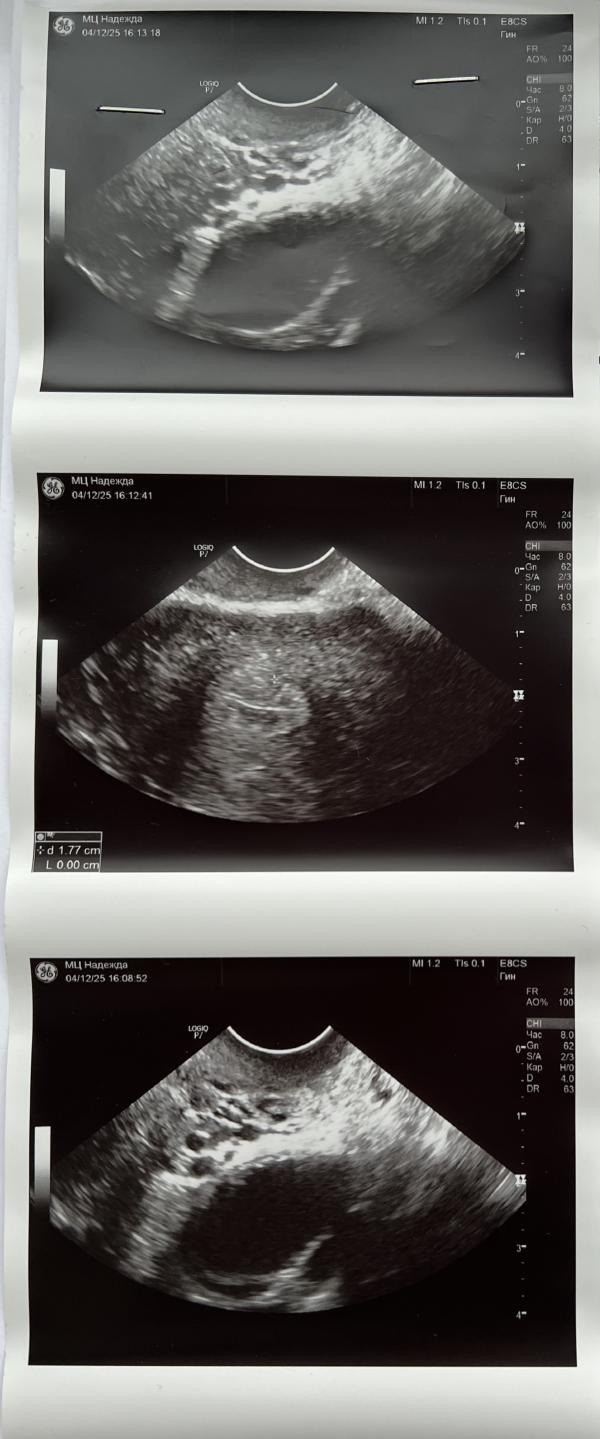

10 ДЦ - ДФ 15 мм (1 фото).

14 ДЦ - якобы ДФ 21 мм (2 фото).

По дурости добавила узи с 14 ДЦ в ИИ, и оно мне выдало «киста ЖТ» 🤦🏽♀️

Теперь меня мучает вопрос, а точно ли это ДФ 21 мм, а не ЖТ…. Ведь у ДФ чуть другая форма, круглая, ровная 🤷🏽♀️

3 фото описание узи на 14 ДЦ.

Ну нее, это не жт на фото.

Это чётко доминантный фолликул, на 3 фото эндометрий в фазе пролиферации, идёт 1 фаза значит.

Готовый к выходу дф более вытянутой формы может быть прям перед овуляцией

на узи у вас точно нет кисты, это фолликул готовится лопнуть.

но фолликул может лопнуть и перерасти в кисту желтого тела. И даже если так и будет-киста желтого тела это просто большое желтое тело, на беременность это никак не влияет)